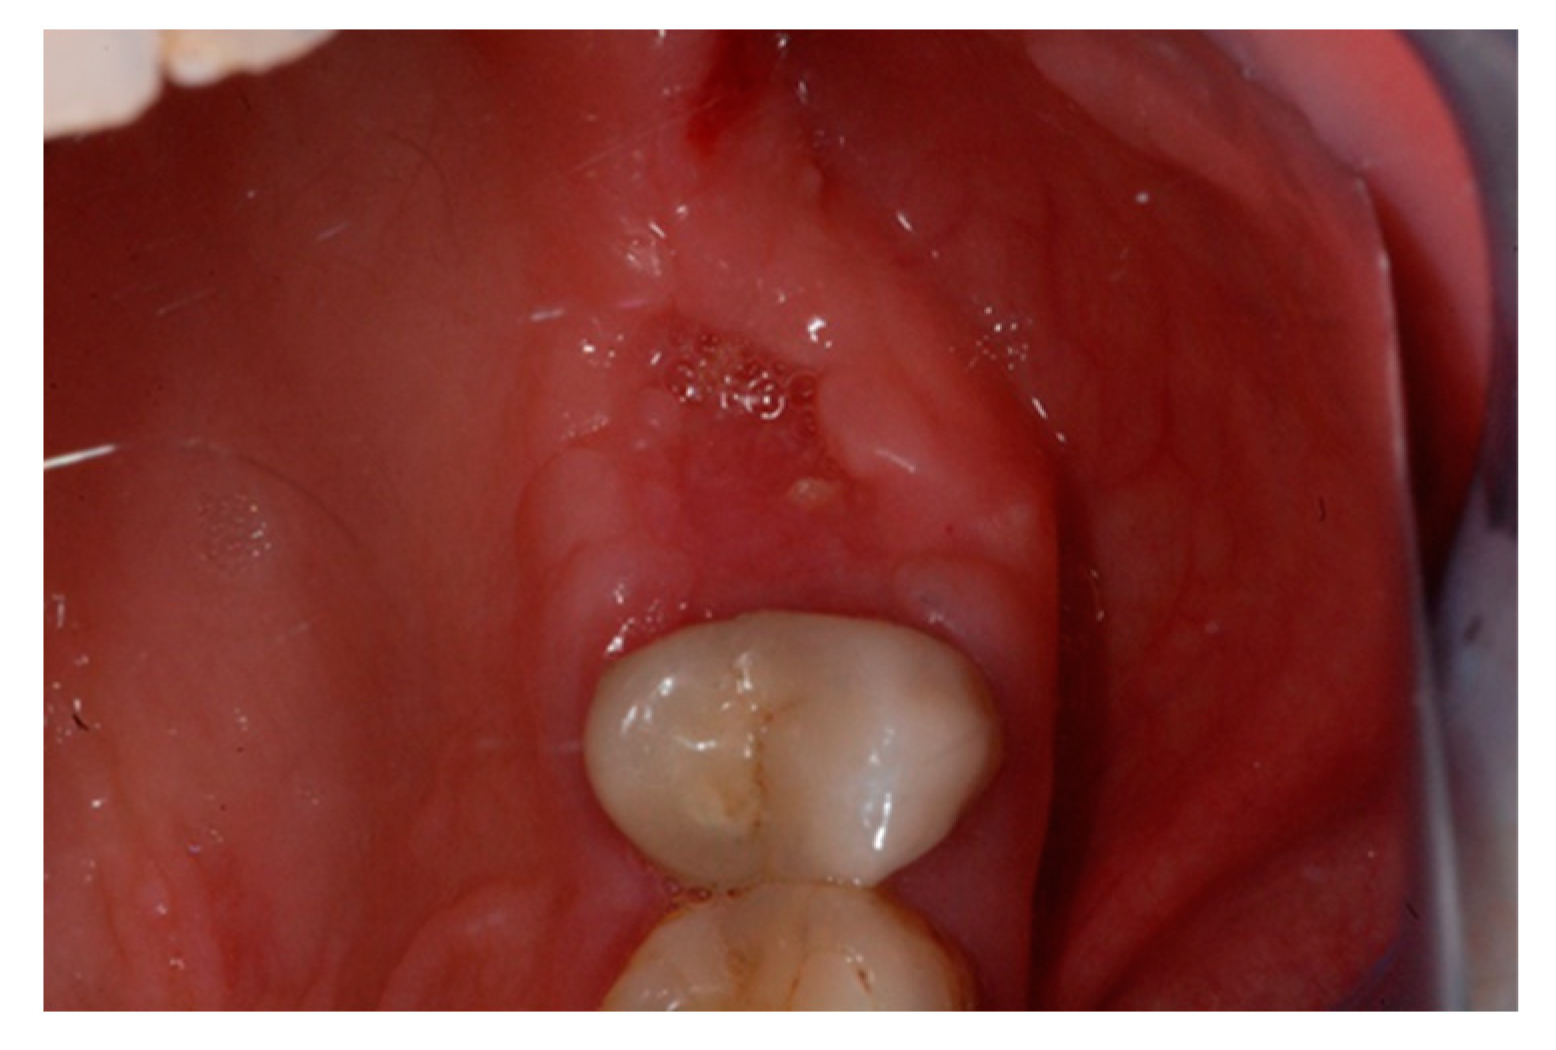

The one-month recall showed a full coverage of the site by epithelialized tissue, thus, indicating perfect healing (Figure 8).

Figure 8.

Intraoperative view of the oral mucosa at one month post tooth extraction. Soft tissues appeared to be completely healed with no signs of bone exposition, considered as a clear sign of BRONJ.